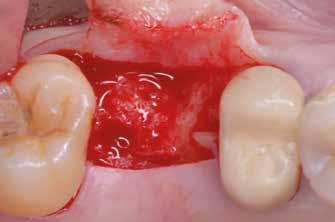

1. ábra: Műtét előtti fogászati panorámafelvétel, amelyen a hiányzó felső állcsont jobb első premolárisát és a szabad véggel rendelkező hidat láthatjuk. — 2. ábra: Az implantátum méreteinek megtervezése CBCT-vel. 3. ábra: Bukkális lágyrészdefektus. — 4. ábra: A biológiai szélesség értékelése a vertikális lágyszövetvastagság alapján. 5. ábra: Palatinális „tekercslebeny” – Palatal roll flap. — 6. ábra: Bredent medical copaSKY 4x10 implantátumbeültetés. 7. ábra: Szubkresztális implantátumbeültetés a várható biológiai szélességnek megfelelően.

(2. ábra). A lágyszövetek értékelése Seibert szerinti I. osztályú csontdefektust állapított meg (3. ábra), ezért a beavatkozáskor palatinális „tekercslebenyt” preparáltunk (palatal roll flap), és implantációt végeztünk, hogy kompenzálni tudjuk a bukkális lágyszövet-behúzódást. Megmértük a vertikális lágyszövetvastagságot, és úgy terveztük, hogy a szubkresztális implantátum beültetése összhangban legyen a biológiai szélesség kialakulásával a transzgingivális gyógyulási periódus alatt (4. ábra)

Sebészeti eljárás

Az eljárást helyi érzéstelenítés mellett végeztük (4%-os articaine-hidroklorid 1:100 000 adrenalinnal). Papillakímélő, U alakú palatális bemetszést végeztünk, teljes vastagságú nyálkahártyalebeny preparálás történt, a lebenyt bukkálisan feltekertük (5. ábra). A lebeny bukkálisan feltekert részén de-epitelizációt végeztük el, amellyel kompenzálni tudtuk a bukkális lágyszöveti defektust. Szakaszos előfúrást végeztünk, és a bredent copaSKY 4x10 implantátumot 30 Ncm behajtási nyomatékkal helyeztük be (6. ábra). Az implantátumot 1 mm-re szubkresztálisan helyeztük be, hogy később szélesebb emergenciaprofilt tudjunk kialakítani (7. ábra). Az egyedi ínyformázó úgy készült, hogy kompozitot vittünk fel a titánbázisra, és így formáztuk a lágyszöveteket a transzgingivális gyógyulási fázis során (8. ábra). Az egyéni ínyformázó tulipán formájú, hogy kialakítsa a kívánt emergenciaprofilt. A lágyszövetet feszülésmentesen zártuk #6/0 nem felszívódó, monofil fonallal (Optilene, B. Braun Deutschland; 9. a–b. ábra). Posztoperatív röntgenfelvétel készült, ami alapján az implantátum a szomszédos fogakkal párhuzamos elhelyezést mutatott (10. ábra). Posztoperatív utasításokat adtunk a páciensnek a műtéti terület körüli szájhigiénia fenntartása érdekében. A beavatkozást követő egy héttel a varratokat eltávolítottuk, és a kezelt terület kielégítő gyógyulást mutatott (11. ábra). A 4 hónap utáni késleltetett terhelést a páciens kívánsága szerint terveztük.